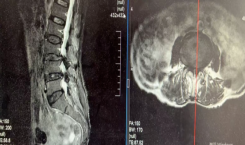

73岁高危老人肾肿瘤!多学科协作+精准腹腔镜,30分钟成功保肾除瘤 ——我院突破...

近日,我院泌尿外科成功为一位73岁高龄、合并严重心律失常的右肾肿瘤患者完成高难度微创手术。医疗团队通过多学科紧密协作,先行植入临时心脏起搏器保障安全,再施行“腹腔镜下右肾部分切除术”,仅用30分钟便精